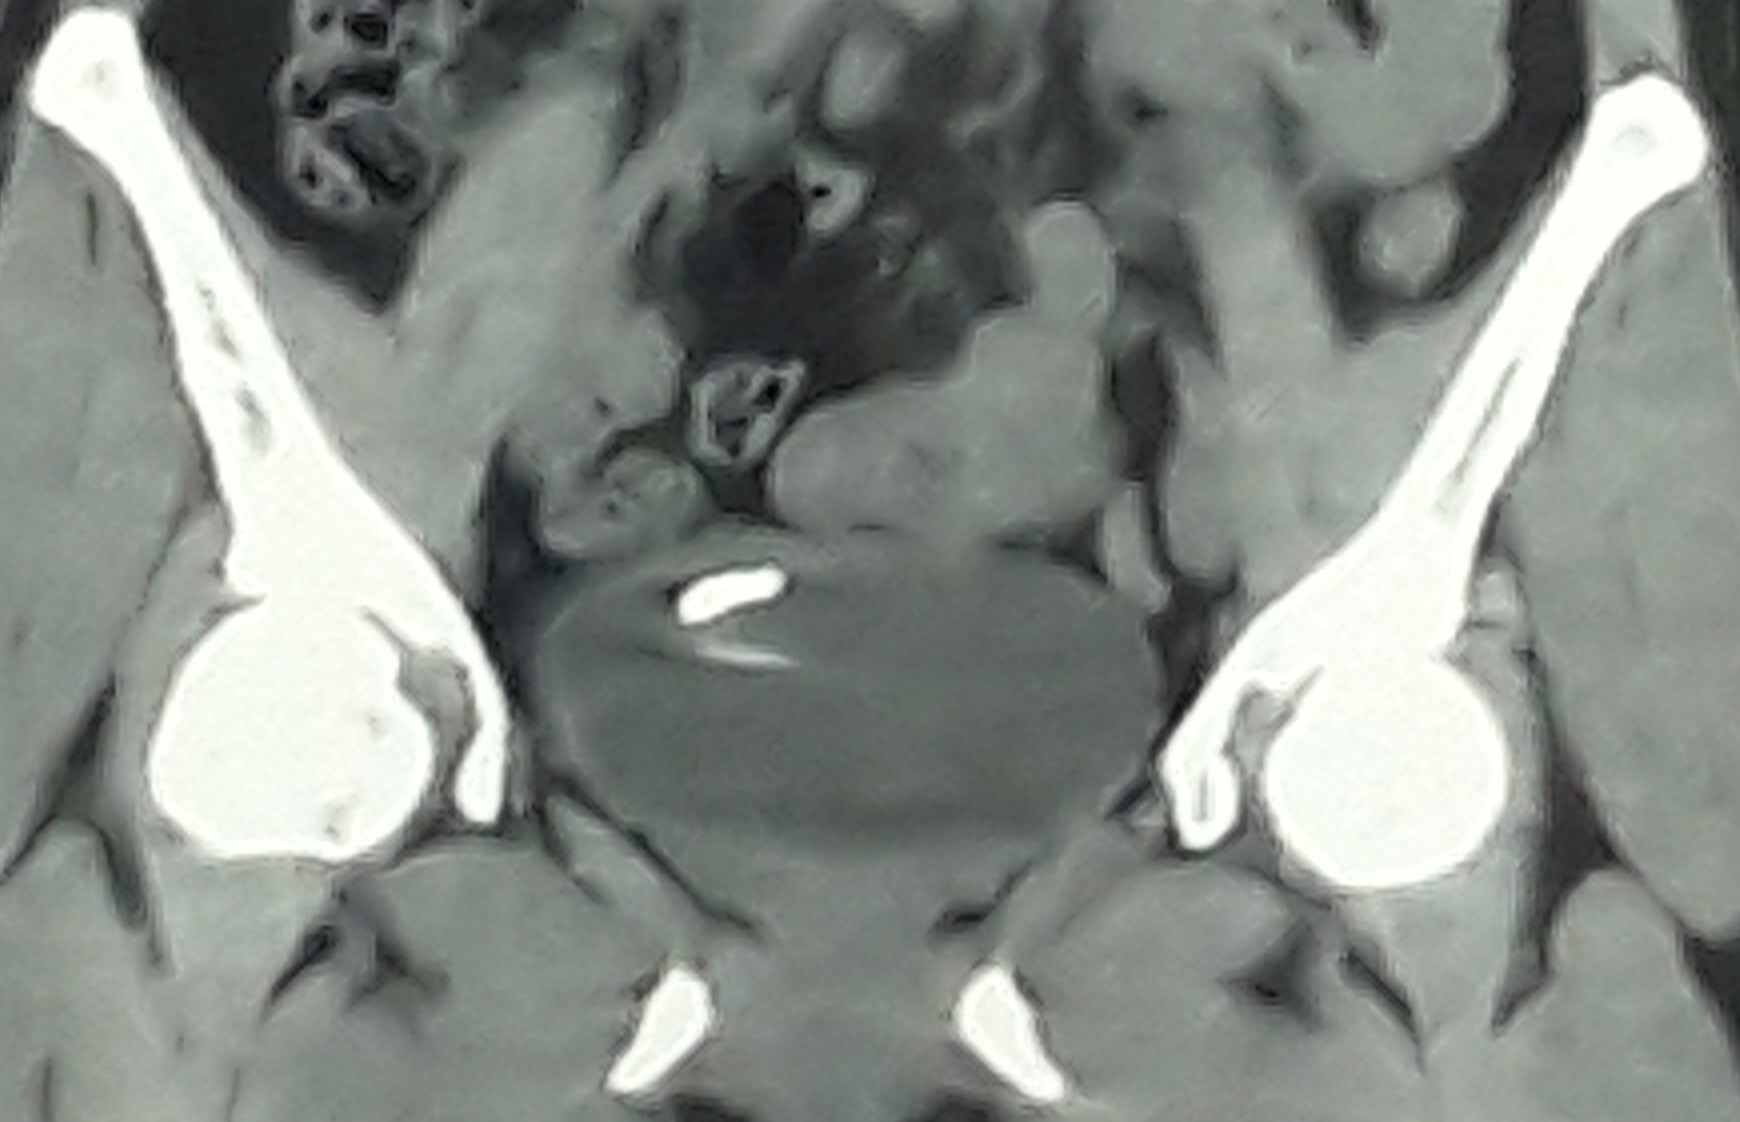

Ảnh chụp CT cắt lớp

Bệnh nhân được tiếp nhận điều trị tại Khoa ngoại, Bệnh viện Tâm Trí Đồng Tháp. Sau khi thăm khám, siêu âm và chụp CT cắt lớp, bác sĩ phát hiện vòng tránh thai đã nằm trong bàng quang. Các bác sĩ Khoa ngoại đã can thiệp bằng nội soi bàng quang, gắp ra một cách an toàn chiếc vòng tránh thai đi nhầm chỗ. Sau nội soi sức khỏe bệnh nhân ổn định, phục hồi tốt, hết tình trạng đi tiểu buốt tiểu gắt.